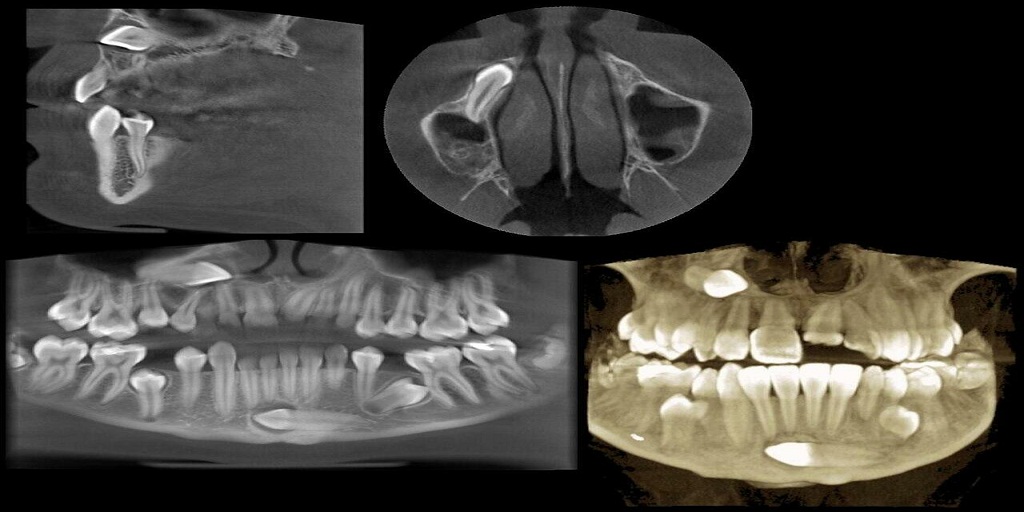

Romexis is the 2D/3D all-in-one dental imaging software from the world-renowned dental imaging equipment manufacturer, Planmeca. As a solution for managing large 3D imaging files, Planmeca Romexis is one of the most powerful dental software platforms available on the market today. It offers a rich selection of tools and features for all needs and specialties.

Romexis brings together all Planmeca equipment at a dental clinic, from CAD/CAM technology to imaging devices and dental units. Romexis 3D software can help you capture, store, access, manage and share dental cone beam images easily. The following features are only some of those that make Planmeca Romexis stand out from the competition.

Romexis software is an all-in-one solution for your dental imaging needs, offering storage and management of numerous types of 2D and 3D imaging. The following is a sample of their available software models:

● 2D Cephalometry (ceph analysis, surgical planning, and treatment follow-ups in 2D).

● 3D Cephalometry (ceph analysis using CBCT images).

● 3D Orthodontics (orthodontic treatment planning in 3D).